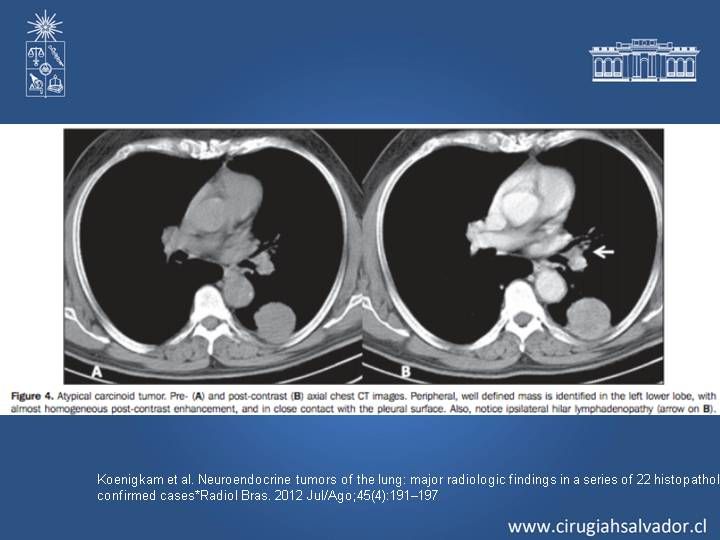

Tumores Neuroendocrino de Pulmón

Cirugía Torácica

| Autor: Dr. Roberto Macchiavello